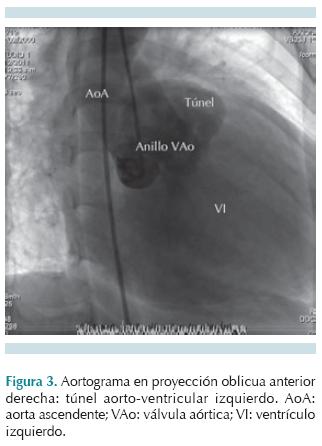

Los datos clínicos suelen evidenciar un soplo sistolodiastólico en foco aórtico, con frémito e irradiación a hueco supraesternal, acompañado de pulsos amplios. En pacientes mayores los síntomas pueden ser similares a una estenosis valvular aórtica; sin embargo, se asemejan más a los de una insuficiencia valvular aórtica con alteraciones en la presión arterial sistémica. La gravedad de los síntomas es variable y los pacientes pueden permanecer asintomáticos por años, hasta desarrollar insuficiencia cardiaca con descompensación súbita y muerte. Los estudios de gabinete iniciales son electrocardiograma y radiografía de tórax en proyección posteroanterior, que muestran datos de hipertrofia ventricular izquierda, pueden indicar datos de sobrecarga diastólica y cardiomegalia con dilatación de aorta ascendente, respectivamente. La ecocardiografía transtorácica es la prueba diagnóstica de elección: en eje largo paraesternal y eje corto demuestran el túnel con dilatación de la aorta ascendente. En Doppler color se observa flujo diastólico originado a nivel de la unión sinotubular alejándose hacia el ventrículo izquierdo. Los túneles que se abren hacia el ventrículo derecho se visualizan en el eje corto paraesternal de la válvula aórtica, mientras que la función del ventrículo izquierdo, que es afectada de forma variable con hipertrofia y dilatación, se evalúa en la vista paraesternal eje corto a nivel de los músculos papilares.3 En casos no concluyentes, en los que no se puedan demostrar con claridad las arterias coronarias, se puede requerir angiografía con catéter. Con estudios avanzados como la resonancia magnética también se pueden demostrar los túneles aorto-ventriculares derecho o izquierdo. El diagnóstico diferencial incluye defecto septal ventricular con lesión valvular, doble lesión aórtica, aneurisma o rotura del seno de Valsalva.

Los estudios de gabinete mostraron en la radiografía de tórax cardiomegalia y crecimiento de los perfiles derecho e izquierdo (Figura 1). El electrocardiograma mostró hipertrofia ventricular izquierda y sobrecarga de volumen en precordiales izquierdas. El ecocardiograma transtorácico en eje largo paraesternal mostró un flujo que se originaba a nivel de la coronariana derecha y se presenta durante la diástole con dirección hacia el ventrículo izquierdo, anillo valvular aórtico dilatado con protrusión hacia el ventrículo izquierdo (Figura 2A). En el ecocardiograma en eje corto paraesternal en modo bidimensional y Doppler color se observó el anillo aórtico dilatado con flujo diastólico entre coronarias derecha e izquierda (Figura 2B). En una vista supraesternal de eje largo se observó una inversión holodiastólica del flujo en la aorta descendente, una pendiente de desaceleración mayor de 3.5 m/s2 en un eje apical 5 cámaras, y un diámetro diastólico y sistólico con Z score +6.1 que confirmaron dilatación ventricular por insuficiencia aórtica. Por este método no fue posible definir la anatomía de las arterias coronarias y, ante duda de túnel aorto-ventricular izquierdo versus aneurisma roto de seno de Valsalva, se decidió realizar cateterismo cardiaco que mostró patrón coronario normal y en un aortograma en incidencia oblicua anterior derecha donde se observó una estructura vascular externa originada en la raíz de la aorta, que correspondía a un túnel aorto-ventricular. La presión telediastólica del VI fue de 21 mmHg (Figura 3). La resonancia magnética apoyó el diagnóstico de túnel aorto-ventricular izquierdo al observarse una comunicación a nivel de la unión sinotubular hacia el ventrículo izquierdo durante la fase diastólica (Figura 4). Se inició tratamiento anticongestivo y se llevó a cirugía donde se encontró una válvula aórtica bivalva, engrosada y con prolapso, túnel aorto-ventricular entre la comisura de las valvas coronarianas derecha y la izquierda, ligeramente por debajo de la unión sinotubular. Se colocó parche tratado con glutaldehido en el extremo aórtico del túnel y una prótesis valvular aórtica tipo St. Jude 25 mm. El paciente permanecía asintomático a los 22 meses de la cirugía.